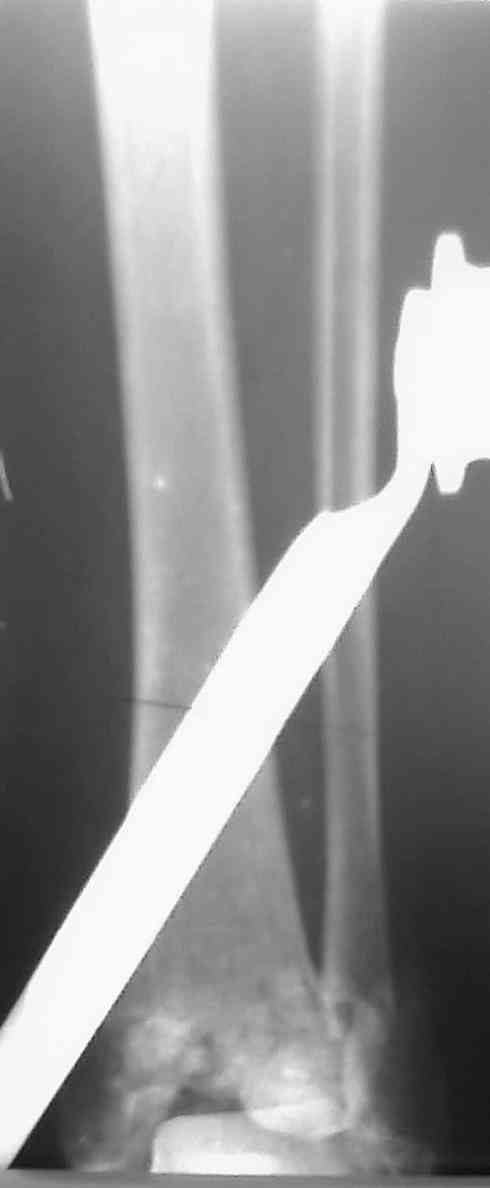

Снова приветствую вас, коллеги. К моменту вступления в обсуждение аксакалов, операция была, увы, выполнена(31.10.07.) Начали с доступа к наружной лодыжке, произвели ее фиксацию спицами, развернули кусок заднего края, наложили дистрактор, затем произвели дистракцию, фиксацию спицами дистального эпиметафиза б/бк,Рентгено-контроль. синтез наружной лодыжки 1/3пластиной. из двух коротких разрезов сформирован канал под медиальную тибиальную пластину LCP. Края ран ушиты без натяжения. Прочувствовать жесткость фиксации винтами с угловой стабильностью не удалось, поэтому дистрактор оставлен на энное время.

На представленных R-снимках не окончательный вид после остеосинтеза. Дистальная опора давила на стопу, пришлось ее сместить проксимально, в рез-те чего, она закрыла щель сустава, последние снимки не информативны.

Честно признаться тяжело на душе после такой операции,-было всё хорошо после первоначальной дистракции, хорошая редукция отломков, после остеосинтеза пластинами появилась подвывых стопы кнаружу, от пластини LCP никакой толку-дистальные винты в зоне излома и дистальный отломок не охвачен, проксимально всего один винт, дистальные винты из м/б кости проходят сквоз сустава и упирается в таранку, стопа в эквинусном положении.Если даже всё обойдется, этот сустав нормально не будет работат.